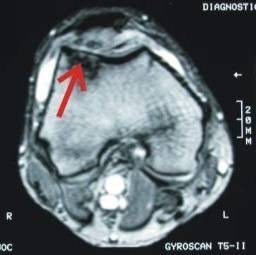

Example of a successful cartilage repair: Full cartilage defect on the patella sliding bearing.

After coverage with a cultivated cartilage, the defect is completely filled and the patient pain-free.